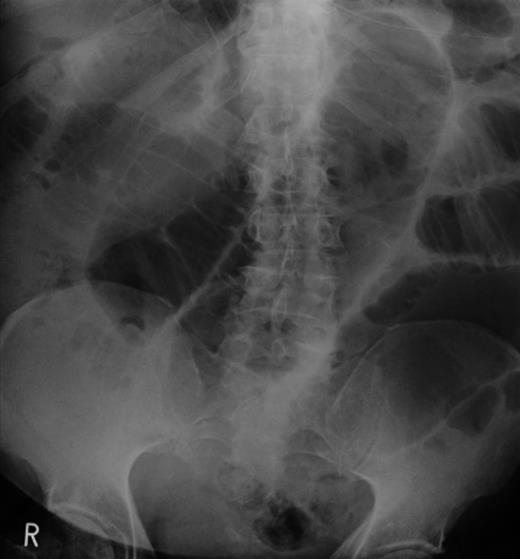

A laparotomy was performed with small bowel resection around the intussusception and primary anastomosis (Fig. 3). The excised segment included a 4-cm lesion (Fig. 4). The excised lesion was composed of areas of spindle and epithelioid cells, and immunohistochemical analysis showed positive staining with CD117, DOG1 and SMA: attributes restricted in the gut to the interstitial cells of Cajal. Genetic analysis detected an exon 11 mutation.